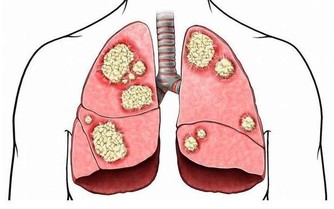

中老年人(45歲以上),由於身體機能的下降和免疫能力逐漸降低,成為我國發病率最高的人群。同樣,也是患癌風險最高的人群。而我國,發病率和死亡率最高的癌症,當屬肺癌!所以,提防肺癌的發生是當務之急!有這「五個信號」的人們,要及時到醫院做檢查,以免耽誤治療!

1、長期咳嗽、痰中帶血

腫瘤生長於管徑較大、對外來刺激落敏感的段以上支氣管黏膜時,可產生類似異物樣刺激引起的咳嗽,典型的表現為陣發性刺激性乾咳,一般止咳藥常不易控製。由於腫瘤組織血供豐富,質地脆,劇咳時血管破裂而致出血。肺癌咳血的特徵為間斷性或持續性、反覆少量的痰中帶血絲,或少量咯血,偶因較大血管破裂導致難以控製的大咯血。

2、低熱

肺癌所致的發熱原因有兩種,一為炎性發熱,癌腫瘤生長時,常先阻塞段或支氣管開口,引起相應的肺葉或肺段阻塞性肺炎或不張而出現發熱,但多在38℃左右,很少超過39℃。

二為癌性發熱,多由腫瘤壞死組織被機體吸收所致。

5、消瘦

肺癌晚期由於感染、疼痛所致食慾減退,腫瘤生長和毒素引起消耗增加,以及體內TNF、Leptin等細胞因子水平增高,可引起嚴重的消瘦、貧血、惡病質。

醫生強調,在病魔面前不可掉以輕心。要想儘早發現肺癌,最有效的辦法就是體檢。

肺癌的篩查手段主要包括:X線胸片+痰細胞學;低劑量螺旋CT;血、痰生物標記物;呼出氣體監測等診斷技術。其中,低劑量螺旋CT檢查已成為肺癌篩查和早期診斷最常用的臨床工具,與胸片相比,它可以提高檢出率,降低肺癌患者的死亡率。